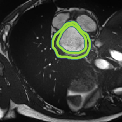

Despite their outstanding accuracy, semi-supervised segmentation methods based on deep neural networks can still yield predictions that are considered anatomically impossible by clinicians, for instance, containing holes or disconnected regions. To solve this problem, we present a Context-aware Virtual Adversarial Training (CaVAT) method for generating anatomically plausible segmentation. Unlike approaches focusing solely on accuracy, our method also considers complex topological constraints like connectivity which cannot be easily modeled in a differentiable loss function. We use adversarial training to generate examples violating the constraints, so the network can learn to avoid making such incorrect predictions on new examples, and employ the Reinforce algorithm to handle non-differentiable segmentation constraints. The proposed method offers a generic and efficient way to add any constraint on top of any segmentation network. Experiments on two clinically-relevant datasets show our method to produce segmentations that are both accurate and anatomically-plausible in terms of region connectivity.